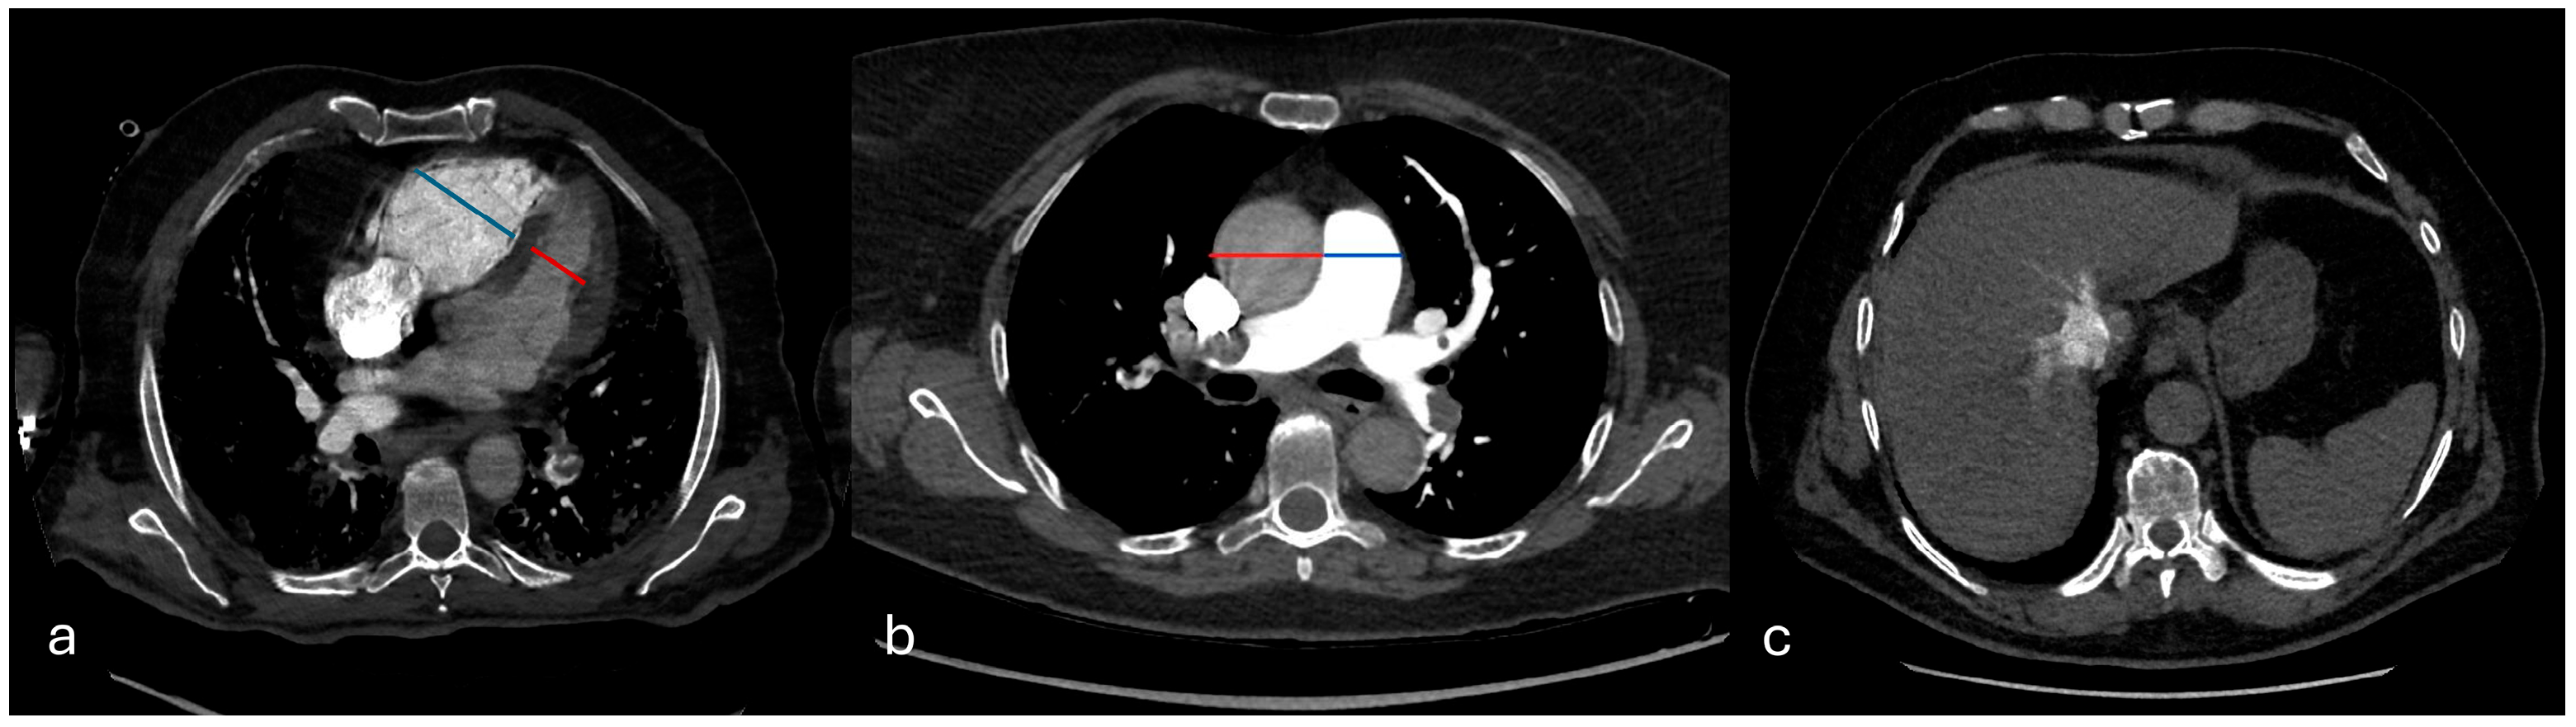

Right ventricular dysfunction (RVD) was evaluated based on three criteria: a right-to-left ventricular short-axis diameter ratio (RV/LV) measured on the same axial slice at the valvular plane, using inner-edge-to-inner-edge calipers, so that both cavities were sampled in the same cardiac phase (normal value < 1), interventricular septal bowing toward the left ventricle (deviation of the interventricular septum was evaluated as follows: normal (convex toward the RV), flattened, and septal bowing (convex toward the left ventricle), and contrast reflux into the inferior vena cava (IVC) graded ≥ 2 on a four-point scale. The main pulmonary artery diameter (PA) and ascending aorta (Ao) diameter were also recorded, and the PA/Ao ratio was calculated (Figure 4).

Figure 4. Signs of right ventricular dysfunction. In (a), the right-to-left ventricular diameter ratio measured on the same axial slice at the valvular plane, using inner-edge–to-inner-edge calipers; in (b), the main pulmonary artery diameter (PA) and ascending aorta (Ao) diameter (PA/Ao ratio); in (c), contrast reflux into the inferior vena cava (IVC).